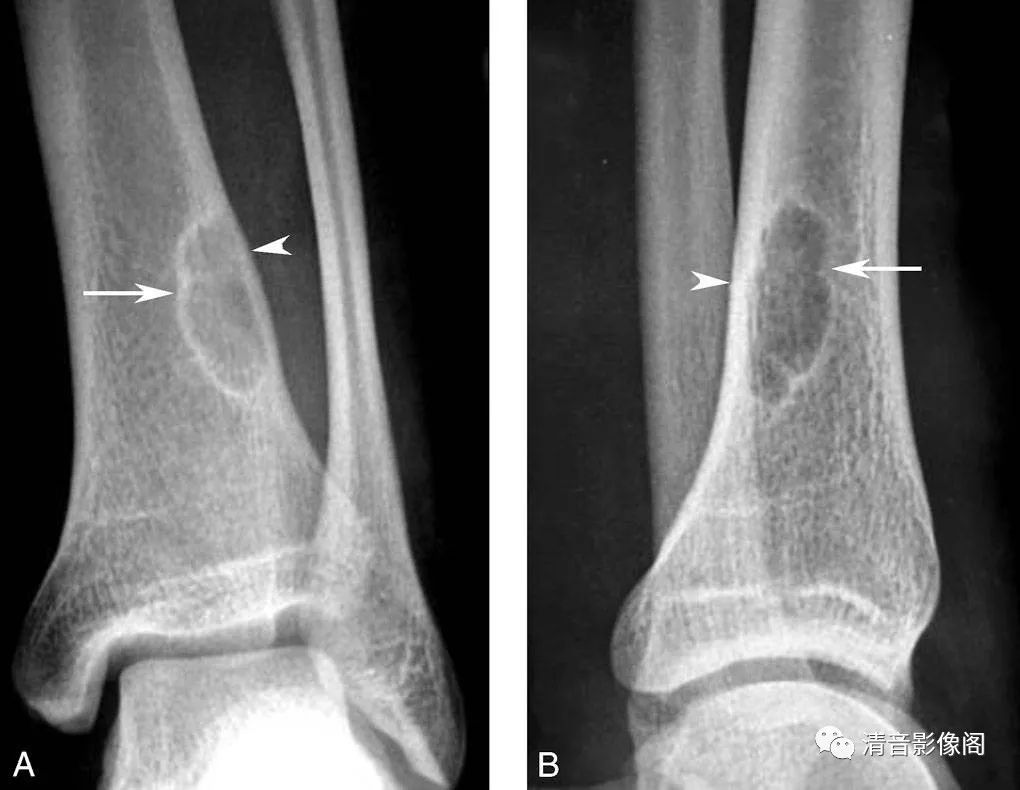

干骺端纤维性缺损

A. 踝关节X线正位;B. 踝关节X线侧位。

男,20岁。干骺端纤维性缺损,表现为皮质内的凹陷性缺损(箭头),周围伴硬化缘(箭),认为是由局部机械性拉力所造成的,若缺损不能修复进一步发展可演变为非骨化性纤维瘤,两者鉴别有一定的难度,一般认为后者硬化缘更宽,灶内有骨棘,呈皮质下膨胀而薄的葡萄串样透亮影。